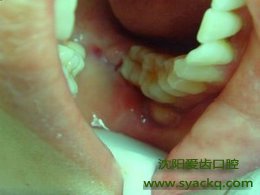

西宁哪家妇科医院最好?1.位置比较正,预计能正常萌出或已经正常萌出者,不嵌塞食物。>>>>>>..推荐阅读:牙齿月白越健康吗

2.智齿冠周软组织没有发炎和疼痛史,智齿没有龋坏者。

3.上下智齿咬合规整。